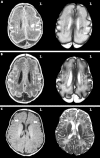

Objective: To describe the magnetic resonance imaging (MRI) characteristics of punctate brain lesions in neonates (number, appearance, distribution, and association with other brain abnormalities) and to relate them to neurodevelopmental outcome.

Results: Punctate lesions were observed in 15/50 preterm and 2/42 term infants. In the preterm group, the number of lesions was < 3 in 20%, 3-10 in 27%, and > 10 in 53%. In 14/15 the lesions were linearly organised and located in the centrum semiovale. Other brain abnormalities were absent or minor--that is, "isolated" punctate lesions--in 8/15 and major in 7/15. In the term group, punctate lesions were organised in clusters and no other brain abnormalities were observed. Isolated punctate lesions were observed in 10/17 infants, and a normal neurodevelopmental outcome was seen in 9/10 (mean follow up 29.5 months). One infant showed a slight delay in language development. In the infants with associated brain lesions (7/17, mean follow up 27.5 months), outcome was normal in only two subjects.

Conclusions: Punctate lesions are predominantly seen in preterm infants, are usually linearly organised, and border the lateral ventricles. Isolated punctate lesions may imply a good prognosis, because most of these subjects have a normal neurodevelopmental outcome so far.